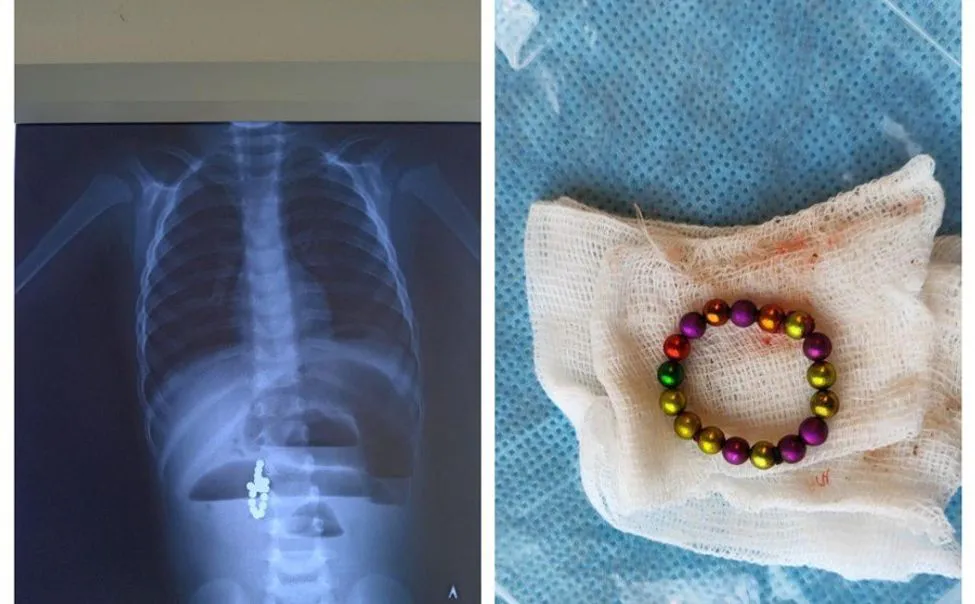

Трое детей были госпитализированы в Республиканскую детскую клиническую больницу. Мальчик пяти лет проглотил два магнитных шарика, девочка шести лет проглотила магнитный шарик и проволоку, а тринадцатилетняя девочка проглотила металлические бусины. Об этом сообщают в Минздраве Чувашии.

Большинство инородных объектов можно удалить эндоскопически, но случаи с магнитами являются особенно сложными и требуют серьёзного хирургического вмешательства. Только благодаря своевременной помощи врачей, удалось спасти детей. Всех их ждёт длительный период реабилитации.